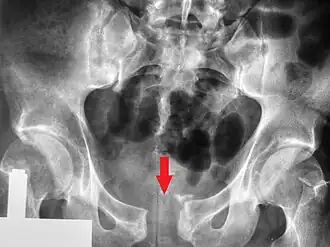

| Radiografia pélvica em que se observa fratura aberta | |

Uma fratura da bacia é uma fratura óssea nos ossos da bacia.[1] Especificamente, o termo denomina qualquer fratura no sacro, nos ossos da anca (ísquio, osso público, ílio) ou no cóccix.[1] O sintoma mais evidente é dor na região pélvica que se agrava com o movimento.[1] Entre as possíveis complicações estão hemorragias internas, lesões na bexiga e trauma vaginal.[2][3]

Entre as causas mais comuns de fraturas na bacia estão quedas, acidentes rodoviários, atropelamento ou lesões por esmagamento direto.[2] Em pessoas mais novas geralmente é necessário um trauma significativo para fraturar a bacia, enquanto em pessoas idosas mesmo traumas ligeiros podem resultar em fraturas.[1] As fraturas da bacia dividem-se em dois tipos: estáveis e instáveis.[1] As fraturas instáveis dividem-se nas de compressão ântero-posterior, compressão lateral, cisalhamento vertical e mecanismos combinados.[2][1] O diagnóstico é suspeito com base nos sintomas e num exame físico e pode ser confirmado com radiografia ou TAC.[1] Nos casos em que a pessoa está alerta e não apresenta dor na região da bacia, geralmente não são necessários exames imagiológicos.[2]